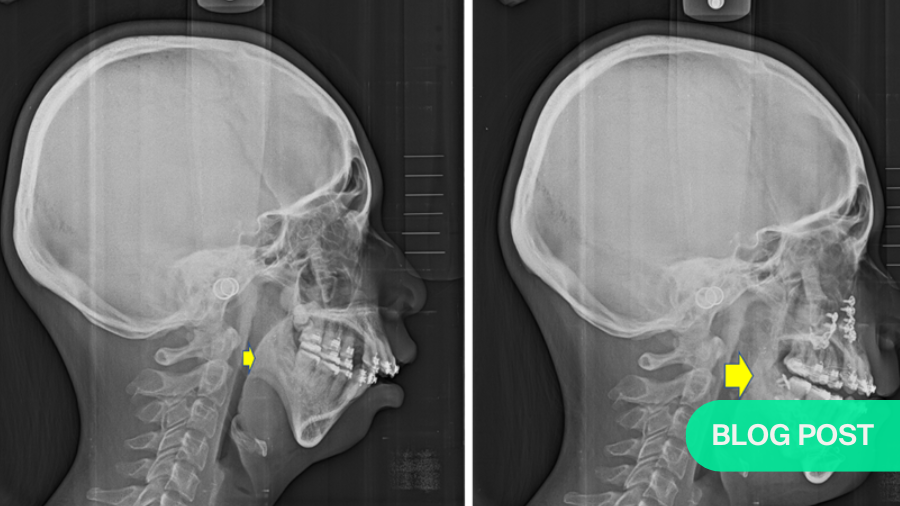

A patient with small chin complaining of sleeping disturbance with snoring, and pre-op AHI: 8.5 was noted (Fig. 2a) underwent segmental Le Lefort I osteotomy with maxilla-mandibular advancement (Fig. 2b). Post-operative airway expansion has been achieved with reduction of AHI (AHI: 2.4) after orthognathic surgery. Three-dimensional airway change shows volume of pharyngeal airway has enlarged from 18965 mm3 to 22899 mm3 peri-operatively (Fig. 2c). The patient was happy with functional and esthetical improvement during the whole treatment. Similar study of airway change could be searched in the literature which addressed patients with cleft receiving orthognathic surgery5.